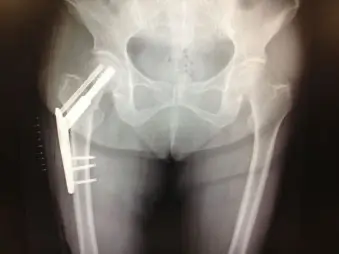

疼痛が持続するため、3週間後に再受診。レントゲン、CTにて右大腿骨頸部骨折を認め、手術目的に入院となった。

GardenⅡ型、PauwelsⅢ型の骨折を認める

大腿骨頸部骨折の治療法はいくつかある。本症例は大腿骨頸部大転子側から小転子にかけて縦方向に骨折線を認め、GardenⅡ型と安定型であるものの、PauwelsⅢ型と剪断力が大きい骨折であった。そのため、保存加療のみで骨癒合は期待できず、手術が勧められた。術式としては、GardenⅡ型であることから、侵襲の大きい人工骨頭置換術よりも、より低侵襲な観血的整復固定術が選択された。

観血的整復固定術には、ハンソンピン、cannulated cancellous screw、compression hip screw (CHS) などの内固定材がある。前2者は複数のピンやスクリューで固定する術式で、骨頭の回旋予防と固定性を高めるために、大腿骨頸部の下方と後方の骨皮質に接するようにピンやスクリューを挿入することが重要である。プレートをスクリューで固定するCHSは大腿骨転子部骨折でよく使用される方法であり、剪断力が大きい場合にも固定性が高く、早期荷重が可能であるが、前2者に比べると侵襲が大きい。ラグスクリュー挿入の際には、カットアウト率を下げるため、Tip-Apex distanceを20mm以下となるようにすることが重要である。

本症例では年齢やADLなどの患者背景のほか、強固な固定性、剪断力を圧迫力に変換、術後の内反変形予防、術後早期荷重が可能という点からCHSを選択した。さらに、回旋予防と荷重による剪断力増強に対する固定性をあげるため、ラグスクリューの頭側にcancellous screwを追加できるつば付タイプを使用した。手術は大きな問題なく終了し、術後2日目より荷重開始。リハビリも順調に進み、歩行できている。